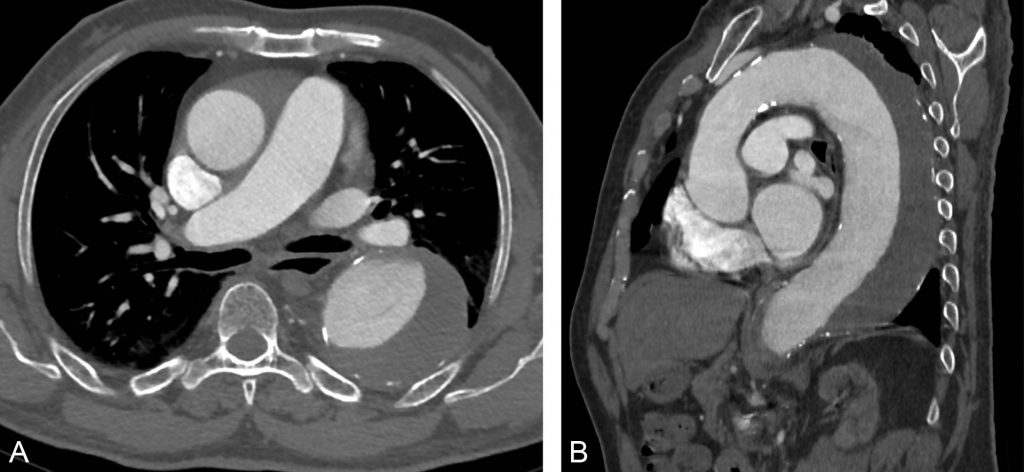

Fig. 36.2. Anévrisme de l’aorte abdominale.

En échographie (A) et en scanner (B), l’aorte apparaît très dilatée avec ici présence de thrombus mural (flèches).

Source : CERF, CNEBMN, 2022.

Fig. 36.3. Anévrisme de l’aorte abdominale.

Les reconstructions TDM frontales (A) montrent la topographie du sac anévrismal par rapport aux artères rénales et à la bifurcation aortique : il s’agit ici d’un anévrisme sous-rénal. Après traitement par mise en place d’une endoprothèse couverte, le scanner en reconstruction frontale montre la prothèse dans la lumière aortique avec son armature de crochets métalliques et la thrombose du sac anévrismal autour (B).

III. Sémiologie

Un anévrisme de l’aorte se présente sous la forme d’une ectasie de la lumière aortique, associée le plus souvent à un thrombus pariétal. En scanner, on perçoit facilement que le diamètre de l’aorte dépasse celui du corps vertébral (cf. figure 36.2B) :

- la lumière aortique circulante apparaît anéchogène en échographie et se rehausse en scanner après injection ;

- le thrombus pariétal apparaît échogène en échographie et ne se rehausse pas en scanner après injection (cf. figure 36.2, A et B).